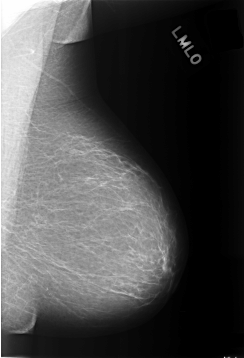

C_0305_1.LEFT_MLO

LEFT_CC LINES 5776 PIXELS_PER_LINE 3888 BITS_PER_PIXEL 12 RESOLUTION 50 NON_OVERLAY

LEFT_MLO LINES 5720 PIXELS_PER_LINE 3904 BITS_PER_PIXEL 12 RESOLUTION 50 NON_OVERLAY